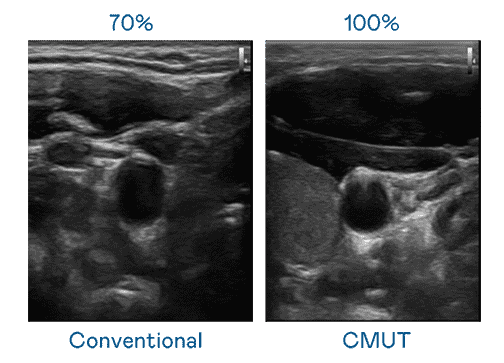

CMUT 技术是一种用电容式微机电元件来产生超音波讯号的技术。。。与传统 PZT 压电式技术相比,,,CMUT 频宽增加 30%,,更宽频的超音波讯号让影像解析度大幅提升,,,,是实现高影像品质医疗超音波扫描、、、、促进精准医疗发展的关键技术。。。。

大频宽带来超清晰影像

超音波影像的解析度高低,,,首先取决于探头能发出的讯号频宽。。。红龙扑克 CMUT 可提供高清晰的超音波讯号,,提供高频宽、、、高灵敏度、、、影像纹理细节更高的超音波影像,,协助医护人员缩短影像判读时间及利用精准的医疗影像进行诊断。。。